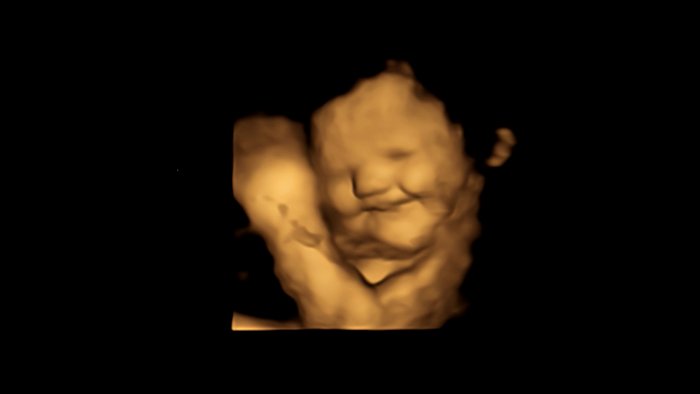

When exposed to the leafy green, the fetus dramatically scowls.

When exposed to carrots, fetuses showed a “laughter-face.” Kale, on the other hand, often led to a “cry-face” response.